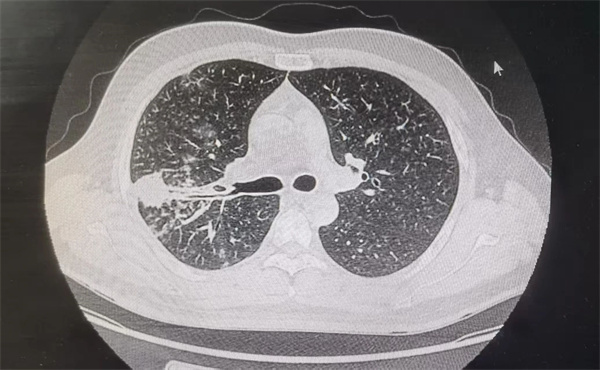

此次手术在医院腔镜中心进行,患者为67岁男性刘某,因左上肺远端出现不规则毛刺并分叶的结节病灶就诊,临床高度怀疑恶性肿瘤。

患者肺部CT影像图

鉴于病灶距离胸膜较远,不适合传统CT引导下穿刺,呼吸内科经充分讨论,决定采用REBUS-GS技术,并制定了详尽的治疗与应急方案。同时,特别邀请北京应急总医院张洁莉主任医师现场指导。